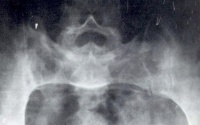

化脓性骶髂关节炎

周围大关节炎症以髋关节最常见。表现为对称性、均匀性关节间隙狭窄,软骨下骨板不规则骨硬化,关节外缘骨刺形成,最后骨性强直。肩关节为第二好发部位,病变情况与髋关节相类似,骨腐蚀主要发生在肱骨头外上方。